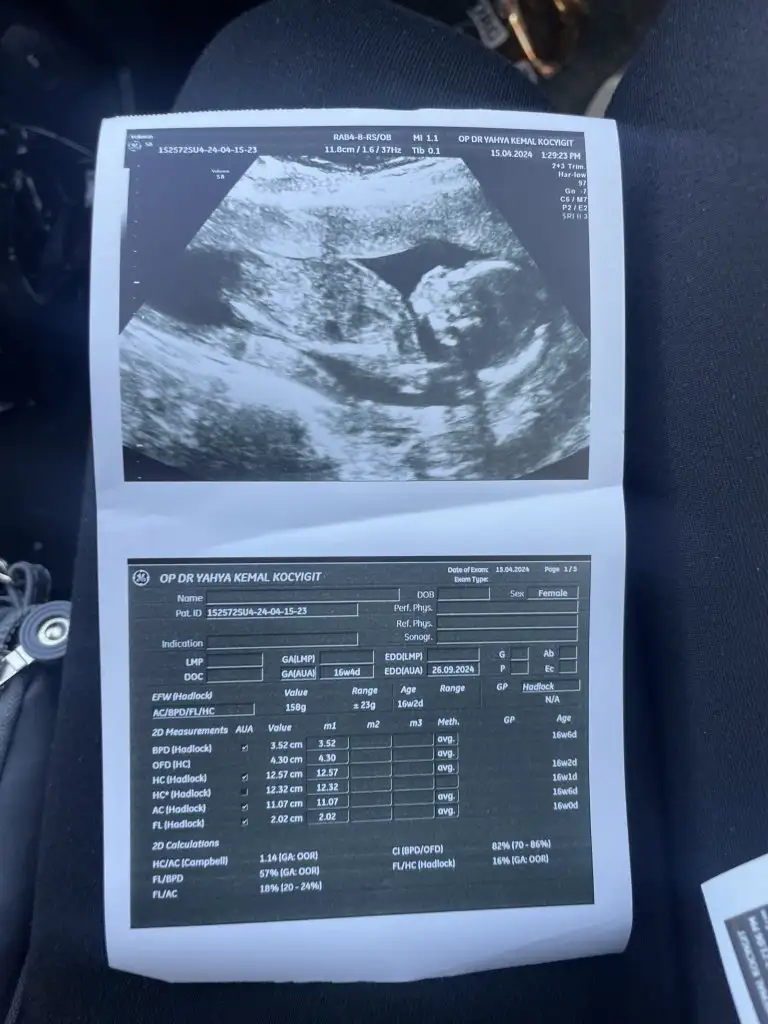

Kızlar sizce cinsiyet ne nuba göre herkez kız diyor kız olsa renkli ultrasonda bu kadar belirgin çıkıntı olurmu

Eklentiler

• IMG-20240418-WA0026.webp

IMG-20240418-WA0026.webp

13,8 KB · Görüntüleme: 88

• IMG-20240421-WA0000.webp

IMG-20240421-WA0000.webp

11,5 KB · Görüntüleme: 91

Fotoya tekrar baktım bence kız bu erkek olması için çizginin yatay değil dik olmasi lazım seni ki yatay gidiyor benim kide öyleydi doktor kız dedi inşallah gönlünden geçen olur

Çizgiden kastınız nedir acaba onu anlayamadım, kendime de bakacağım da :)